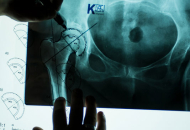

Workshop Spiron® Vietnam

K-implant-Workshop in Privatklinik